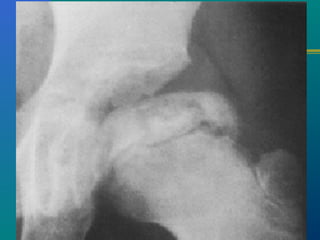

TB HIP- X-RAYTB HIP- X-RAY

 Osteoporosis

 Travelling acetabulum

 Dislocated hip

 Mortar and pestle appearance

 Perthes type

 Protrusio acetabuli

 Destruction of head